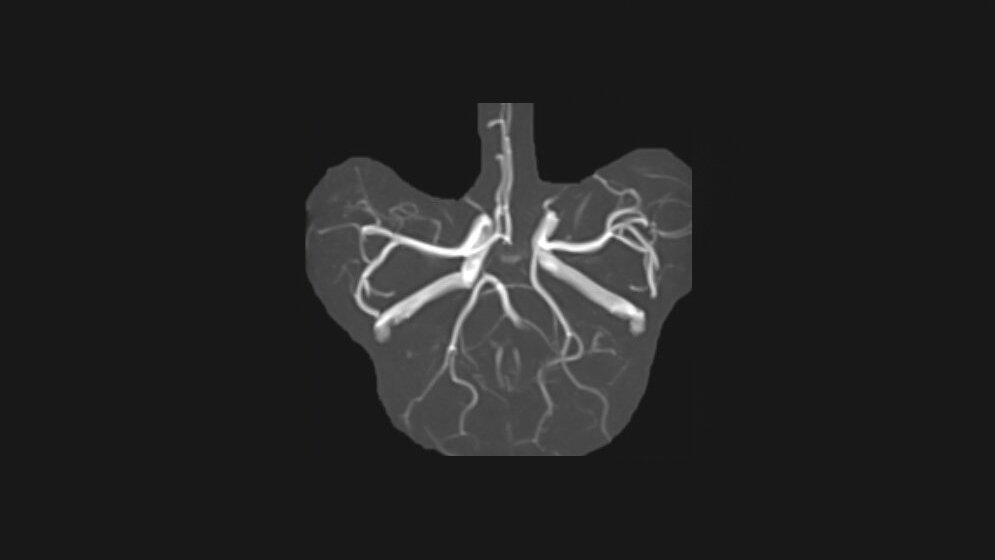

Die symmetrische zirkuläre Konfiguration des Circulus arteriosus cerebri kommt nur in 42,1 % (bei Erwachsenen) vor. Der Hauptunterschied zwischen der fetalen und erwachsenen Anlage ist der Gefäßdurchmesser des Ramus communicans posterior.

The symmetrical, circular configuration of the circulus arteriosus cerebri is present in only about 42,1 % (in adults). The main differences between the fetal and adult disposition is the diameter of the posterior communicating artery.